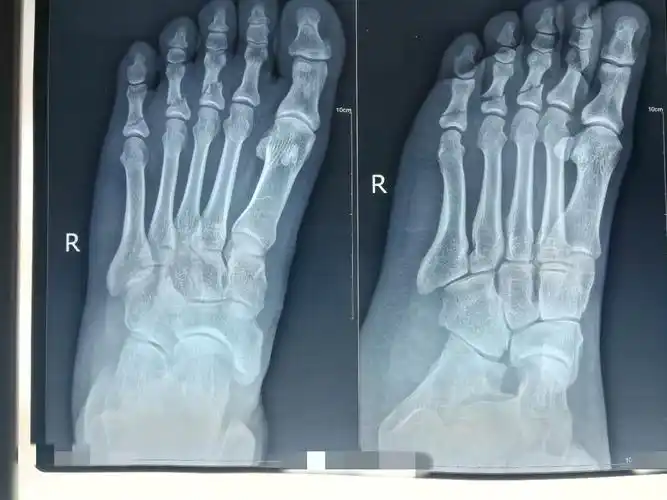

主要症状等):12,12,6日被电单车给撞到右脚脚腕处肿起,去医院ct拍过后

右足第3,4,5趾骨骨折